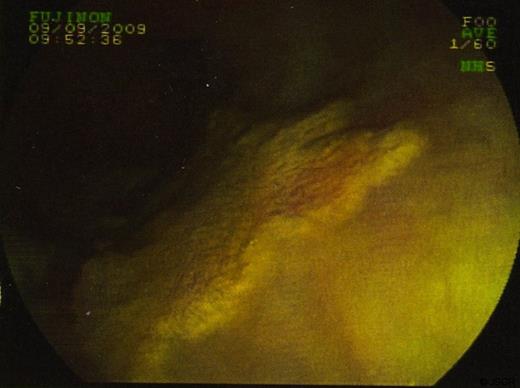

In September 2009 the patient underwent a colonoscopy and oesophagogastroduodenoscopy (OGD). Colonoscopy was unremarkable. However, views of the oesophagus on OGD showed what was thought to be a superficially spreading tumour, 35cm from the incisors and 5 cms in length. Barrett’s oesophagus was also seen. (figure 1 & 2)

Biopsies were taken and sent to histopathology. In some sections the cells viewed had small bland nuclei with foamy cytoplasm. They were negative for mucin stain and negative for epithelial markers. There was no dysplasia or malignancy. This picture was consistent with xanthalasma. Other biopsies of surrounding tissue showed a picture consistent with Barrett’s oesophagus. (Figure 3 & 4)